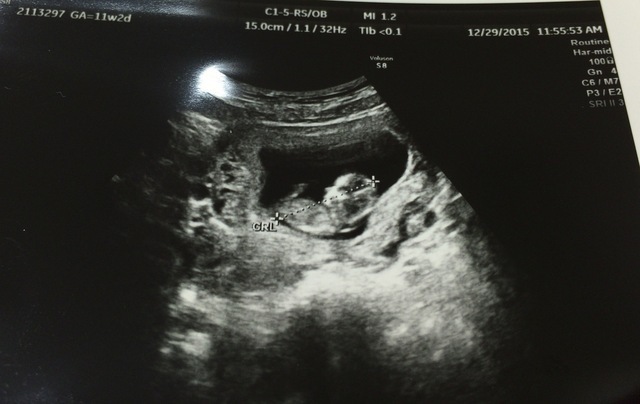

11週2日(11w2d・女の子)|ayane52 さん(19歳)

エコー写真撮影時のエピソード:

ハッキリと体全体が映っていてとても感動しました。 遅めのつわりが始まってとてもつらい時期でした。

旦那は毎回健診に来てくれていて心強く、また、パパとしての自覚もちゃんとあって、この人と結婚して良かったと思いました。

つわりはいつか終わりが来ると散々言われました(笑)。 遅く始まったつわりは7ヶ月まで続きました…。 でも、みんなが支えてくれたので乗り切ることができました!! みんなには感謝です!